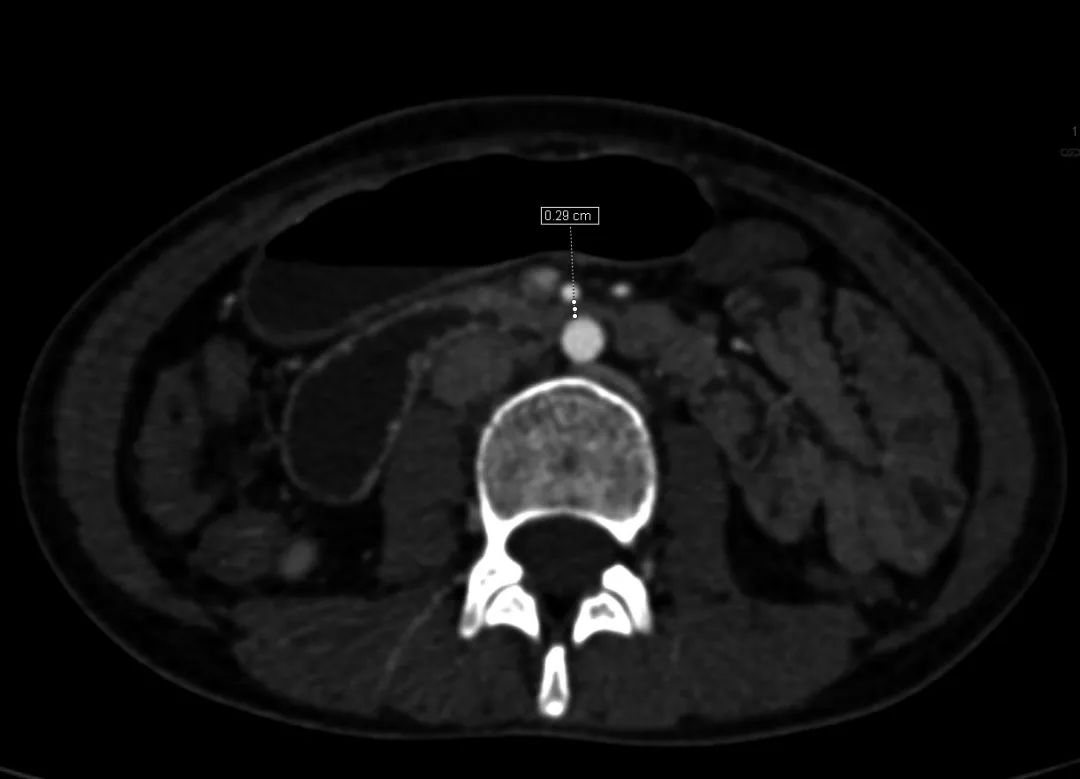

X 线钡餐常有十二指肠水平部脊柱中线处中断。主动脉和肠系膜上动脉之间的夹角20°。主动脉与肠系膜上动脉之间的距离2.9mm。

●主动脉和肠系膜上动脉之间的夹角≤25°是最敏感的诊断指标,特别是当主动脉与肠系膜上动脉之间的距离≤8mm时。